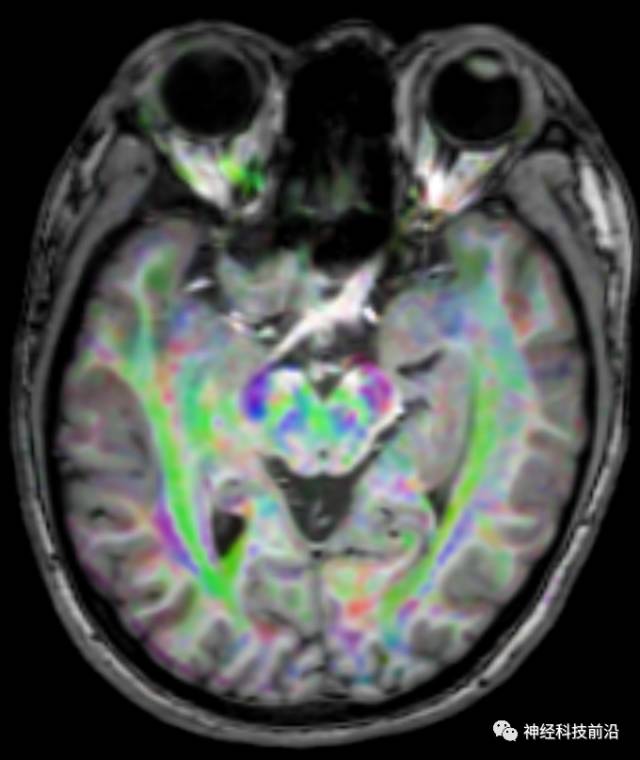

DTI原始图像

DTI原始图像与T1融合图像

下面为皮质脊髓束的走形及位置